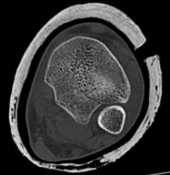

Partial articular fracture—plate fixation Case description A 53-year old man injured his right ankle in a mot…